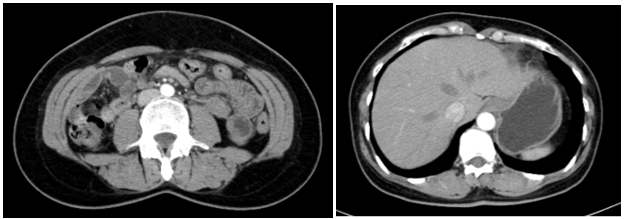

Siêu âm:

Thùy phải: kích thước bình thường, nhu mô có vài nhân hỗn hợp âm, lớn nhất kích thước 3x3mm và có nhân giảm âm, vôi hóa ngoại vi kích thước 3x4mm (TIRADS 4), nhân đồng âm bờ đều, kích thước 4x6mm.

Thùy trái: kích thước bình thường, nhu mô có vài nhân hỗn hợp âm, bờ đều, lớn nhất kích thước 8x9mm (TIRADS 3).

Hình 1: Hình ảnh nhân giảm âm thùy phải tuyến giáp (TIRADS 4)